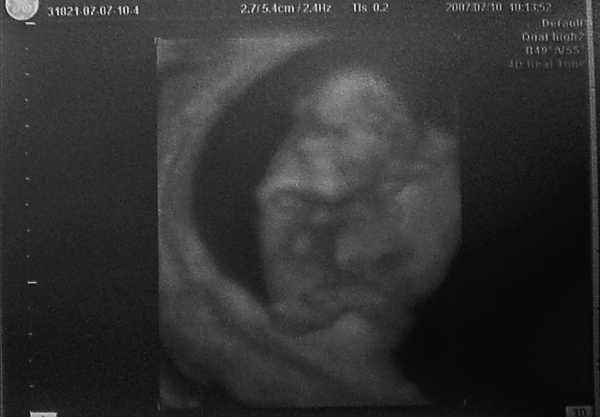

11hét+5napos ficánka:)